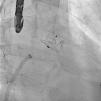

A 61-year-old man, with a history of coronary heart disease and percutaneous coronary intervention, with stents in the right coronary and circumflex arteries, was referred to our center for left atrial appendage (LAA) closure. He had atrial fibrillation with high thromboembolic risk (CHA2DS2VASc=4) and oral anticoagulation was formally contraindicated because of recurrent severe bleeding. Selective angiography of the LAA (Video 1) showed a close relationship between the LAA (Figure 1, asterisk) and the circumflex artery (Figure 1, arrow), well defined by the previously implanted stents. A computed tomography scan performed after a previous episode of diffuse alveolar hemorrhage showed similar findings (Figure 2, arrow). A 22-mm Amplatzer Amulet device was successfully placed, with no residual leak. Intraoperative monitoring by transesophageal echocardiography and post-procedural radioscopy confirmed the close relationship between the device and the circumflex artery (Figures 3 and 4, Videos 2 and 3), which is vital to keep in mind in order to prevent complications during the procedure.